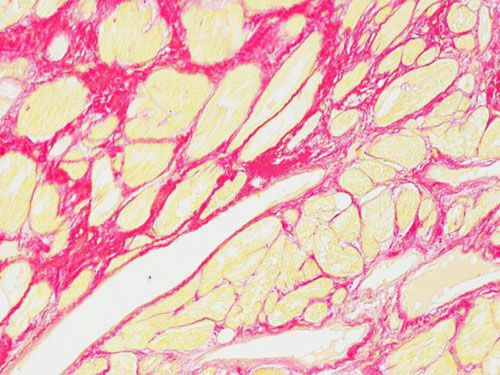

實驗結果展示:

H心肌

在普通光學顯微鏡下膠原纖維呈紅色,其他組織成分被染成黃色。